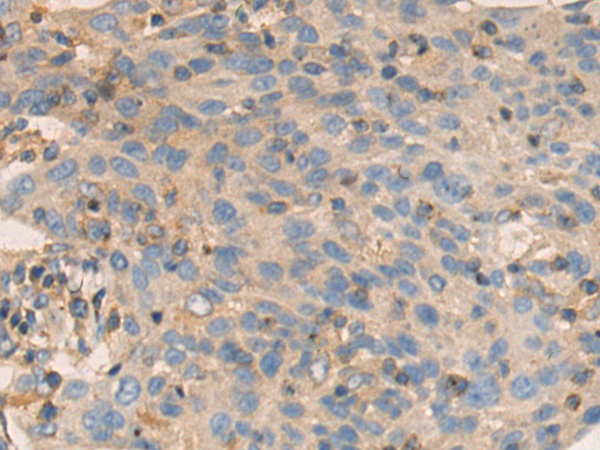

分类: 科研抗体货号: P13787别名: PKACB; PKA C-beta应用: WB,IHC反应种属: Human, Mouse, Rat